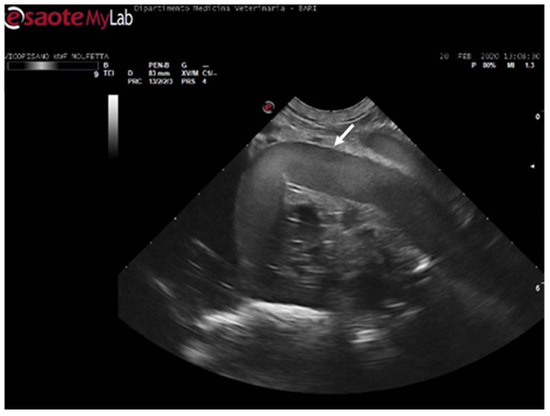

In four turtles (13, 8%), the ultrasound examination revealed a significantly slow blood flow, but no flow was detected using Color Doppler ultrasound. The renal vessels and subclavian vessels, which were closer to the acoustic windows, were easily identified. However, examination of the vessels and the coelomic cavity through the ventral cervical acoustic window was challenging due to significant gas-related disorders. Consequently, visualization of the aortic arch and the heart was precluded. Similarly, it was impossible to locate the mesenteric vessels and differentiate the hepatic parenchyma along with its associated circulation. The presence of larger emboli, some up to 5 mm in size, hindered the visualization of vessel walls, and the gas-induced artifacts, such as comet tails, were so pronounced that they masked the view of tissues and vascular regions (Figure 7) (Video S2). Those ultrasound images have been a consistent finding in the subjects previously categorized by radiographic exams as having moderate GE, implementing Parga’s method [17].

Figure 7.

Ultrasound scan from the right prefemoral window revealing several clusters of large emboli attached to the hepatic vessels (empty white arrows). The artifacts generated by their presence (white arrow) make it challenging to visualize deeper structures.